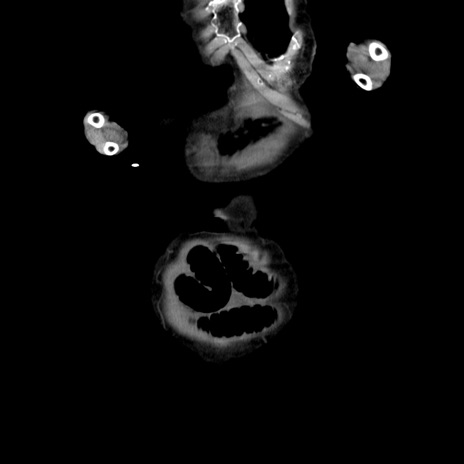

横断像

【症例】80歳代女性

【主訴】嘔吐、腹痛

【現病歴】数時間前より嘔吐あり。心窩部痛出現し、徐々に右下腹痛あり。その後も数回嘔吐あり救急搬送となる。

【既往歴】左大腿骨頚部骨折手術

【身体所見】腹部は膨隆しているが軟らかく圧痛なし。腸雑音はやや亢進。

【データ】WBC 12000、CRP 19.05